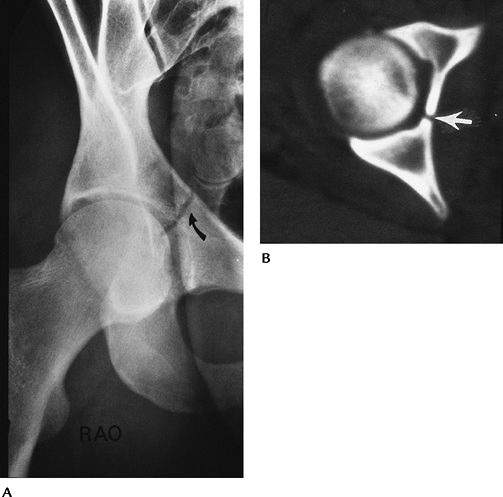

Trauma: Fracture/Dislocation—Dislocation of the Hip

-

Hip dislocations account for 5% of all skeletal dislocations.

Mechanism of injury—high-velocity trauma, usually in young adults

Posterior dislocations—10 times more

common than anterior. Compressive force to foot or knee with hip

flexed. Posterior acetabular fractures are common. -

Anterior dislocations—forced abduction and external rotation. Femoral head and anterior acetabular fractures are common.

Up to 75% have multiple other injuries.

Most complete dislocations are obvious on the AP view of pelvis or involved hip.

CT is useful for complete evaluation of the joint space and associated fractures, especially after reduction.

![]() |

FIGURE 4-12 AP radiographs of posterior (A) and anterior (B) dislocations. Note the displaced femoral head fragment (arrow) in (A).

FIGURE 4-13 (A) CT image of a posterior dislocation. Direction of the force (line with arrowhead). Small posterior rim fracture (open arrow). (B) CT image after reduction of an anterior dislocation with fractures of the femoral neck and anterior acetabulum (arrows).